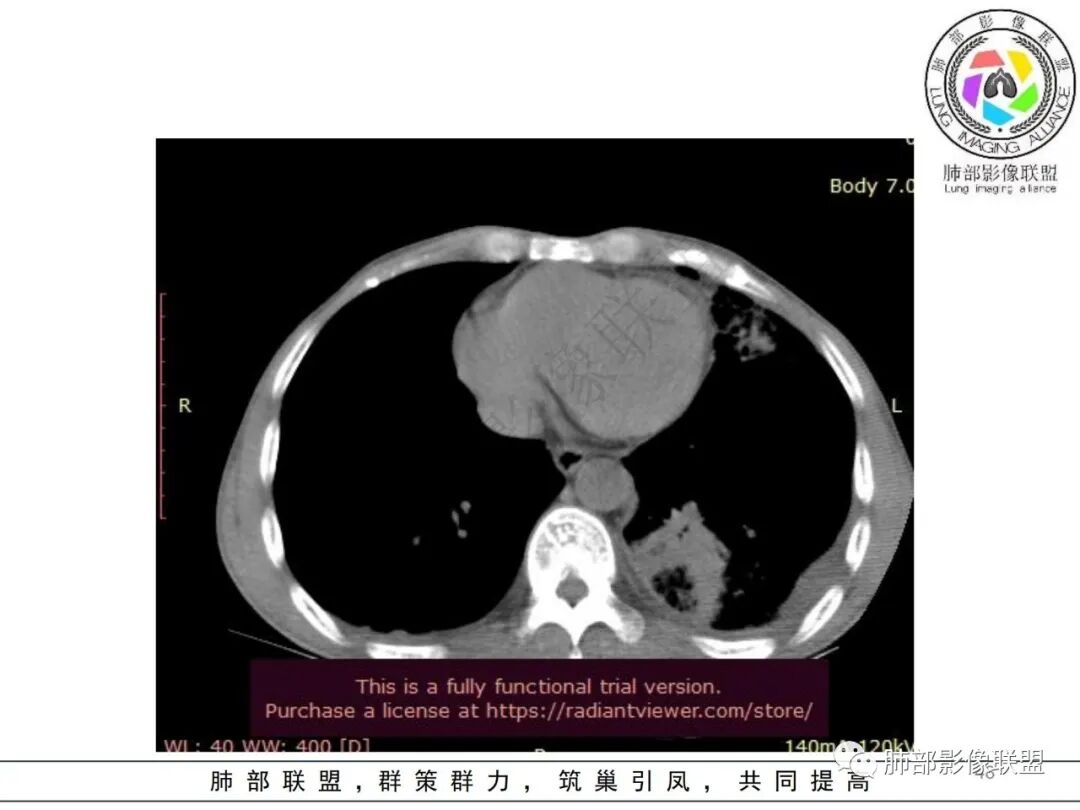

糖尿病除了是肺克好发因素外,同样也是类鼻疽好发因素,差别是肺克多合并肝脓肿,类鼻疽少

但是肺克肝脓肿血播到肺的,看过很多,没有类似晨读那样表现的,今天晨读不是太典型的血播影像表现;复查的影像就很典型

影像表现:双肺多发结节、实变影,大部分病灶边界不清,随机分布趋势,左下肺“反晕征”,似有形成空洞趋势。左侧胸腔积液。治疗后复查 ,大部分病灶吸收好转,呈较为典型血播分布,肝脏低密度块影,边界不清,符合肝脓肿。

综合分析:结合症状及实验室检查,均提示本例为感染性病变;海南居住史首先会让我们考虑是否为类鼻疽,类鼻疽主要为血道播散,此时判断病灶为气道还是血道有重要鉴别意义。首次检查片分析气道、血道均有,没有薄壁气囊,结合临床PCT等实验室检查,肺炎克雷伯杆菌感染的可能性增大。复查片显示肝脓肿,加之糖尿病,临床诊断趋于明朗化。血培养及痰培养均可见肺克雷伯杆菌,诊断明确!